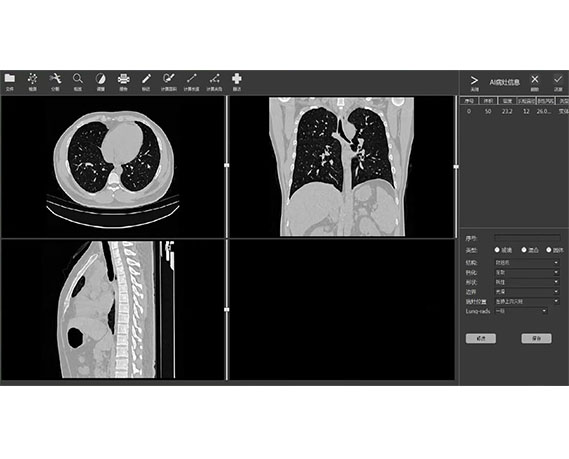

ART-Plan™ Artificial Intelligence Contouring